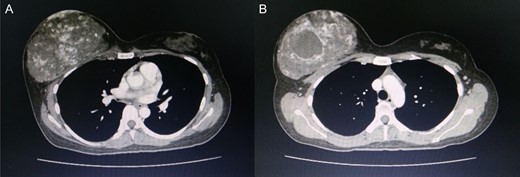

Computed tomography of the chest revealed a hypervascular mass in the right breast measuring 13.7 cm abutting the pectoralis muscle (A) cystic change measuring 5.3 cm in the mass is visible (B).